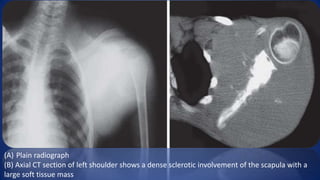

(A) Plain radiograph

(B) Axial CT section of left shoulder shows a dense sclerotic involvement of the scapula with a

large soft tissue mass